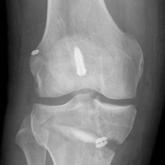

ArticleApplying Military Strategy to Complex Knee Reconstruction: Tips for Planning and Executing Advanced SurgeryAuthor:Thomas M. Deberardino, MDPublish date: July 5, 2017Complex knee restoration for injured soldiers follows a similar paradigm as for high-end civilian athletes. The military healthcare paradigm often ...Read More